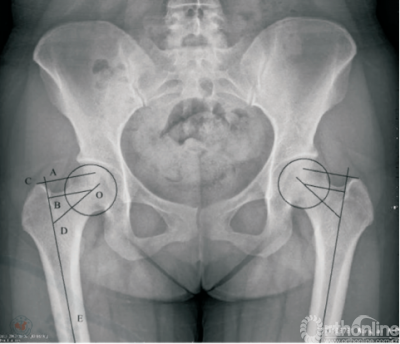

二、标记方法(图1)

在骨盆正位X线上使用中日友好医院影像归档和通信系统(picturearchivingandcommunications System,PACS)(CarestreamHealth.inc.Canada)工具作如下标记:(1)确定股骨头中心;(2)作股骨近端的解剖轴线,从股骨头中心引出直线垂直于解剖轴线,其长度为股骨的偏心距;(3)从大转子顶点作股骨近端解剖轴线的垂线,该垂线与股骨偏心距线平行;(4)经股骨头中心作股骨颈的轴线,与股骨近端轴线交于D点;(5)测量两平行线之间的距离,偏心距及颈干角。如图1,AB的长度是大转子顶点至股骨头中心的垂直距离或称为大转子高度(greater trochanterheight,GTH),大转子顶点位于股骨头中心上方为正值,在股骨头中心下方为负值。

图1 骨盆正位X线片,AE为股骨的解剖轴线,C为大转子顶点,从C点作AE的垂线,交点为A;O为股骨头旋转中心,从O点作AE的垂线,交点为B;OD为股骨颈的轴线。AB的长度是大转子顶点至股骨头中心的垂直距离或称为大转子高度(GTH),大转子顶点位于股骨头中心上方为正值,在股骨头中心下方为负值(OB为偏心距,角ODE为颈干角)